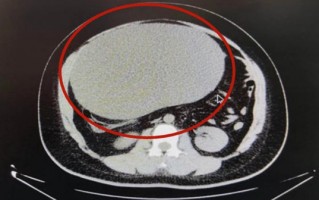

女子以为发胖肚中取出16斤囊肿 比足球大!医生称若局部膨隆要重视 科学动态

女子以为发胖肚中取出16斤囊肿 比足球大!医生称若局部膨隆要重视

女子以为发胖肚中取出16斤囊肿 比足球大!医生称若局部膨隆要重视...

科学动态 2022-11-21 578 #肿瘤 #肥胖